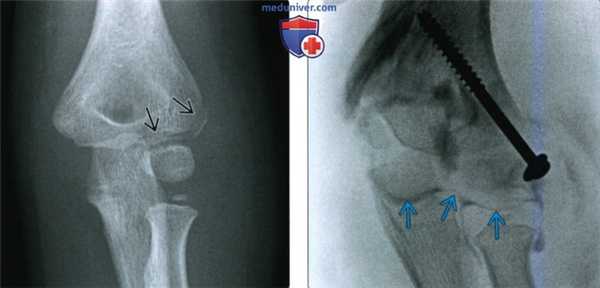

(Слева) На боковой рентгенограмме у четырехлетнего мальчика определяется надмыщелковый перелом плечевой кости после падения на выпрямленную руку. Обратите внимание на смещение головки кзади относительно линии вдоль переднего коркового слоя дистального эпиметафиза плечевой кости. Положительный симптом жировой подушки подтверждает внутрисуставную природу перелома. Следовательно, это действительно чрезмыщелковый перелом.

(Справа) На передне-задней рентгенограмме у этого же пациента не видна линия перелома, что является характерным для этой возрастной группы, кроме случаев с переломом с более значительным смещением.

(Слева) В боковой проекции у женщины 87 лет после падения определяется повреждение Гартланда II типа с задним смещением мыщелков плечевой кости относительно диафиза и задним угловым отклонением, но с сохранением контакта с задним кортикальным слоем.

(Справа) На снимке в боковой проекции у девятилетнего ребенка определяется полное смещение кзади мыщелков плечевой кости и отсутствие контакта между отломками, составляющими повреждение Гартланда III типа. Поскольку перелом не переходит на мыщелки, он является истинным надмыщелковым переломом.